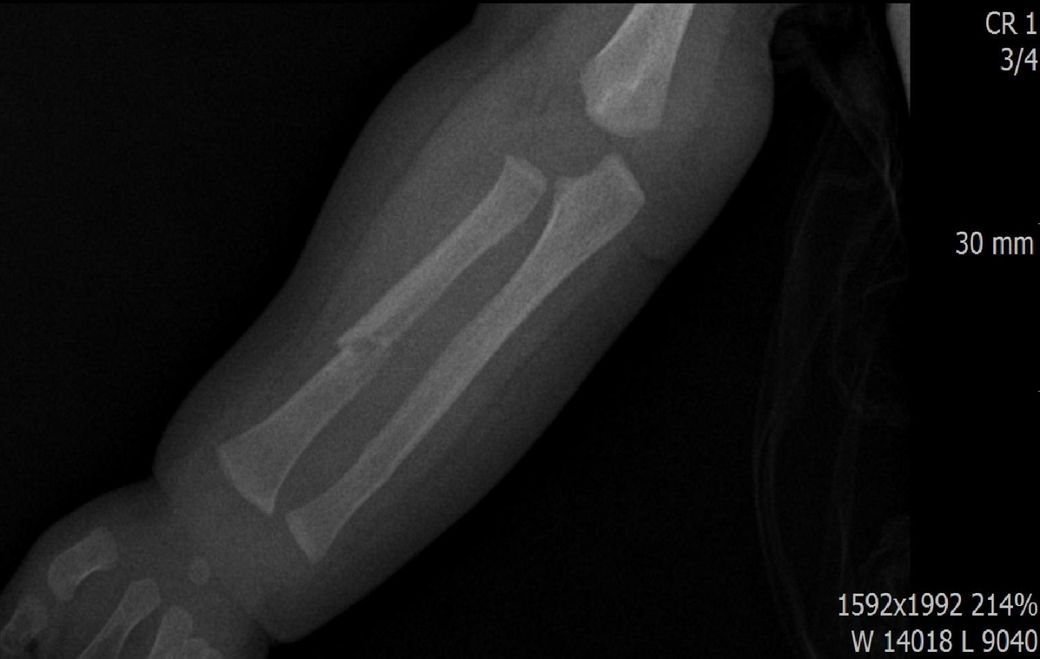

다름이 아니라, 첨부드린 엑스레이(X-ray) 사진처럼 골절 사실을 알게 되고 골절 발생 시점 대략적으로나마 추정시기를 파악하려고 문의 드리게 되었습니다

1) 3월 30일 촬영한 X-ray만으로 정확한 골절 시기를 100% 특정하는 데에는 한계가 있다는 점 충분히 인지하고 있기에 촬영날짜 기준으로 대략적으로 어느정도 시점에서 발생되었을 것으로 추측(ex 당일, 7~10일전, 7~14일 전, 10일 ~ 20일전, 14일 ~ 30일전 등등등)되는지 이해하고 싶습니다.

• 1번 째 사진

엑스레이 만으로 골절 발생 시기를 정확히 특정하긴 어렵지만 뼈의 염증 반응, 골막 반응, 골흡수 신생 정도를 통해 대략 추정은 가능합니다. 보통 급성 골절은 1~7일 이내, 골절선이 희미해지고 골막 반응이 보이면 10~20일 전후 뼈 융합이 일부 보이면 3~4주 이상 경과로 추정할 수 있습니다. 3월 30일 촬영 기준, 골절선의 형태와 신생골 유무에 따라 7~21일 내외의 외상으로 판단되는 경우가 많아요!

골절의 정확한 시기를 예측하기는 어려움이 있으나, 뼈의 골절선이 뚜렷하게 관찰된다면 0~7일 이내의 가능성이 있고 흐린 가골이 관찰되거나 골막의 일부 반응이 관찰된다면 7~14일 이내, 가골이 형성중인것이 관찰된다면 2-3주 이상의 골절시기를 대략적으로 유추해볼 수 있습니다.

골절의 상태를 보고 골절선이 선명하고 부위에 가골이 형성되지않았다면 보통 일주일 이내, 골절선이 보이지만 주변 부위에 가골이 조금씩 있다면 2주 이내, 골절선이 잘안보이고 가골이 보인다면 한달 이내로 판단 할 수 있습니다.

지금과 같이 엑스레이상 골절이 잘 보이는것으로 보아 2주 이내에 특별한 이슈가 있을만한지 생각해보시길 바랍니다^^